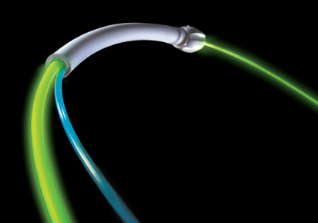

- Daha sonra kamera yardımı ile GreenLight fiber optiği işlem yerine kadar ilerletir.

- Doktor idrar akışını engelleyen prostat dokusunu buharlaştıracaktır. Hemen buharlaşmayan bazı ölü dokular, ameliyatınızdan sonraki birkaç gün içerisinde idrar yolu ile atılacaktır.